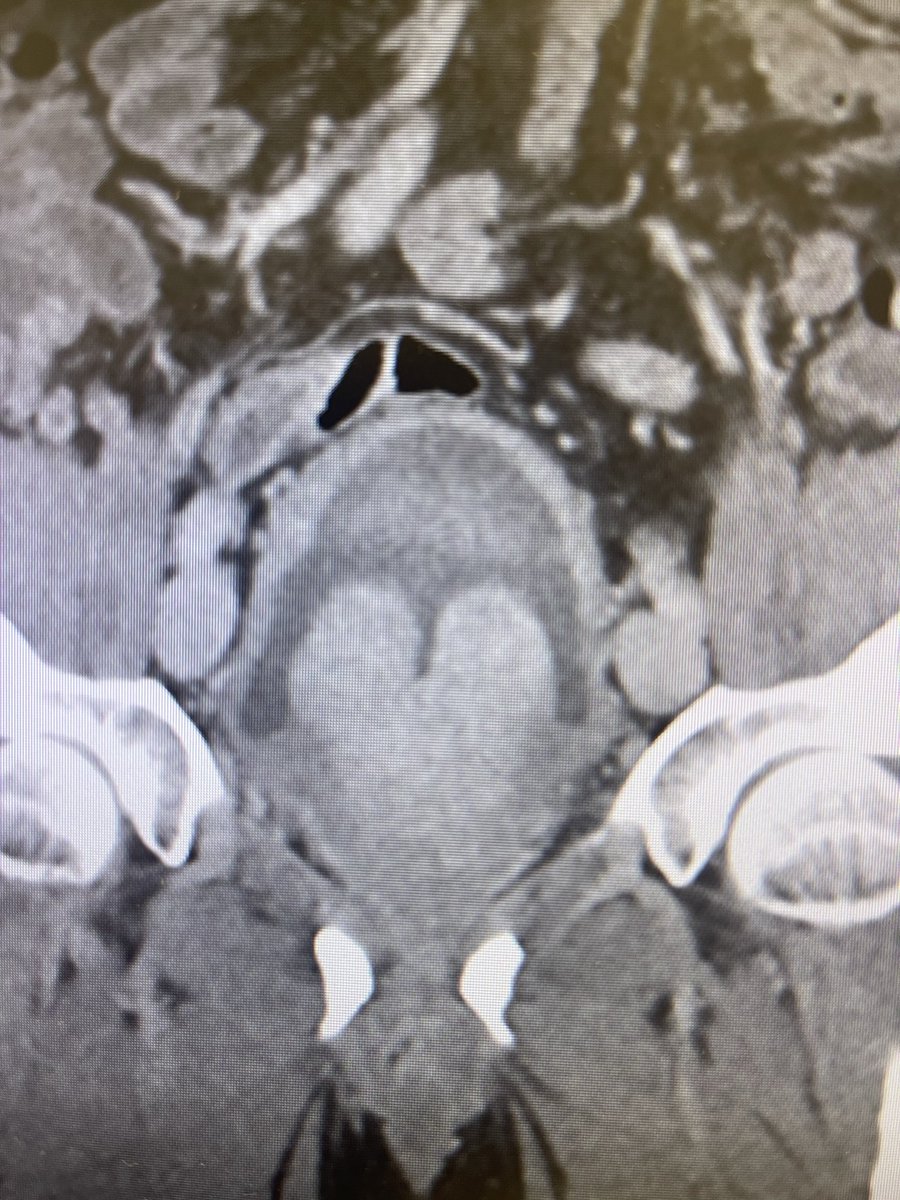

First ThuFLEP procedure successfully performed in Chile with Urolase+ Premium We are proud to share that the first #ThuFLEP procedure in Chile using the Urolase+Premium laser system has been successfully completed at @FelixHfb , with the strong support of our trusted partner IMV MED CHILE. The surgery was performed by Dr. @JIgnacioAcuna and involved a prostate of 50 cc with a non-simple anatomical configuration, further complicated by cystolithiasis with a 17 mm bladder stone. Despite these factors, the entire operation was completed in just 45 minutes. The patient was discharged within 24 hours, underscoring the efficiency and favorable recovery profile of the procedure. @JIgnacioAcuna highlighted the performance of the #DissectPulse mode, noting its precision in anatomical dissection, controlled tissue interaction, and effective hemostasis. According to his feedback, the laser performed excellently and efficiently throughout the case. We sincerely thank IMV MED CHILE for their professional support and collaboration in bringing advanced Thulium Fiber Laser (TFL) technology to Chile. Congratulations to @JIgnacioAcuna and the entire team at @FelixHfb on this achievement. #UrolasePremium #ThuliumFiberLaser #LaserUrology #Endourology #ChileHealthcare #VPGLaserOne